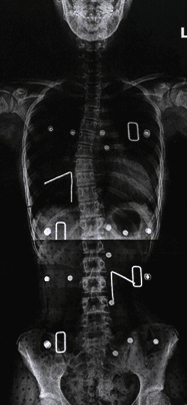

척추측만증(척추옆굽음증)

정상적인 척추는 정면에서 보았을 때 반듯하게 골반 위에 얹혀져 있어야 합니다.

하지만 반듯해야 할 척추가

S자나 C자 모양으로 휘어지는 증상과 동시에 척추 마디마디가 회전하여 틀어지는 변형을 함께 동반

하기도하는데 이러한 척추의 변형을

‘척추측만증’

이라고 합니다.

보존적 치료

운동치료를 통해 잘못된 자세교정 및 몸의 균형을 잡습니다. 만곡이 20도보다 작으면 3∼4개월마 다 정기적인 관찰이 필요하고, 20∼40도는 보조기를 착용하는 치료가 필요합니다.

수술적 치료

만곡이 40도 이상인 경우에는 척추고정술을 통해 수술적인 치료를 시행합니다.

교정전

교정후